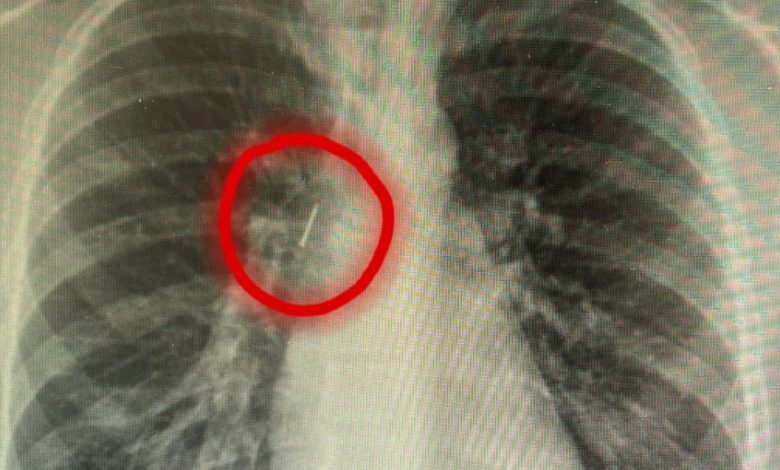

وفي حالتين، استقر الدبوس في القصبة الهوائية الرئيسية اليمنى، بينما تموضع في الحالة الثالثة في القصبة الهوائية الرئيسية اليسرى، وهي مواقع خطيرة استدعت عمليات جراحية فورية تحت التخدير العام.